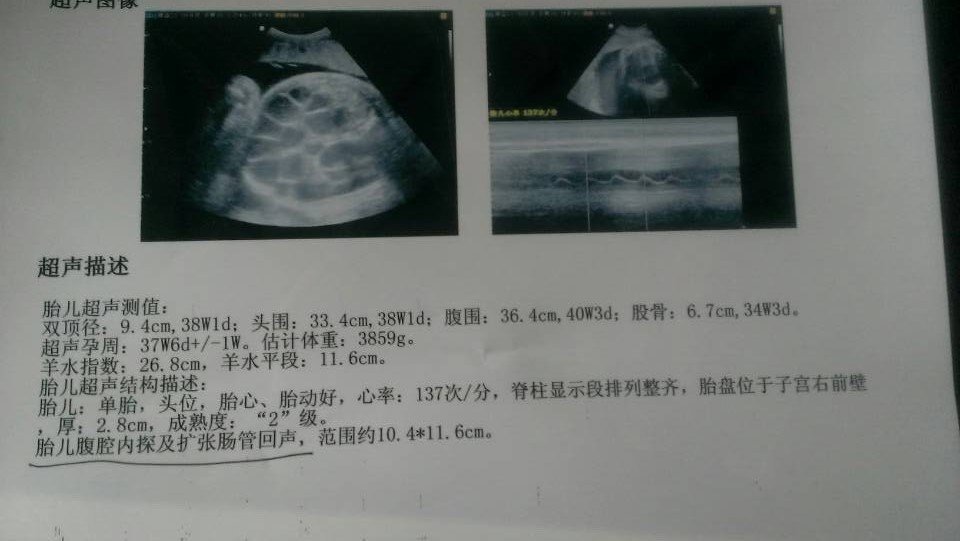

你好,你两次的检查都显示胎儿消化道异常,肠管扩张等,不能绝对排除是消化道发育畸形,如先天性的肛门闭锁,肠道梗阻性病变等引起。建议胎儿在肚子里面,检查比较困难,可以结合磁共振检查看看是否与偶占位性病变等。如果肛门闭锁很难检查出来。